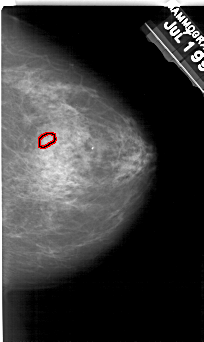

A_1944_1.RIGHT_MLO

RIGHT_MLO LINES 5491 PIXELS_PER_LINE 3391 BITS_PER_PIXEL 12 RESOLUTION 43.5 OVERLAY

FILE: A_1944_1.RIGHT_MLO.OVERLAY

TOTAL_ABNORMALITIES 1

ABNORMALITY 1

LESION_TYPE CALCIFICATION TYPE PLEOMORPHIC DISTRIBUTION CLUSTERED

ASSESSMENT 4

SUBTLETY 3

PATHOLOGY BENIGN

TOTAL_OUTLINES 1

BOUNDARY